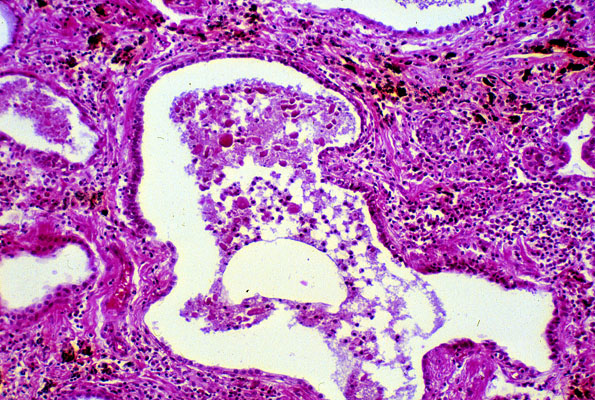

Honeycomb lung

Honeycomb lung, may be seen in a variety of conditions including UIP, DIP, DAD, and organic dust exposure etc. There is no recognizable normal lung tissue due to extensive restructuring of airspaces with obliteration of small airways, extensive fibrosis, and cyst formation. There are dilated abnormal airways containing mucinous material and inflammatory cells, with interspersed areas of fibrosis and chronic inflammation.